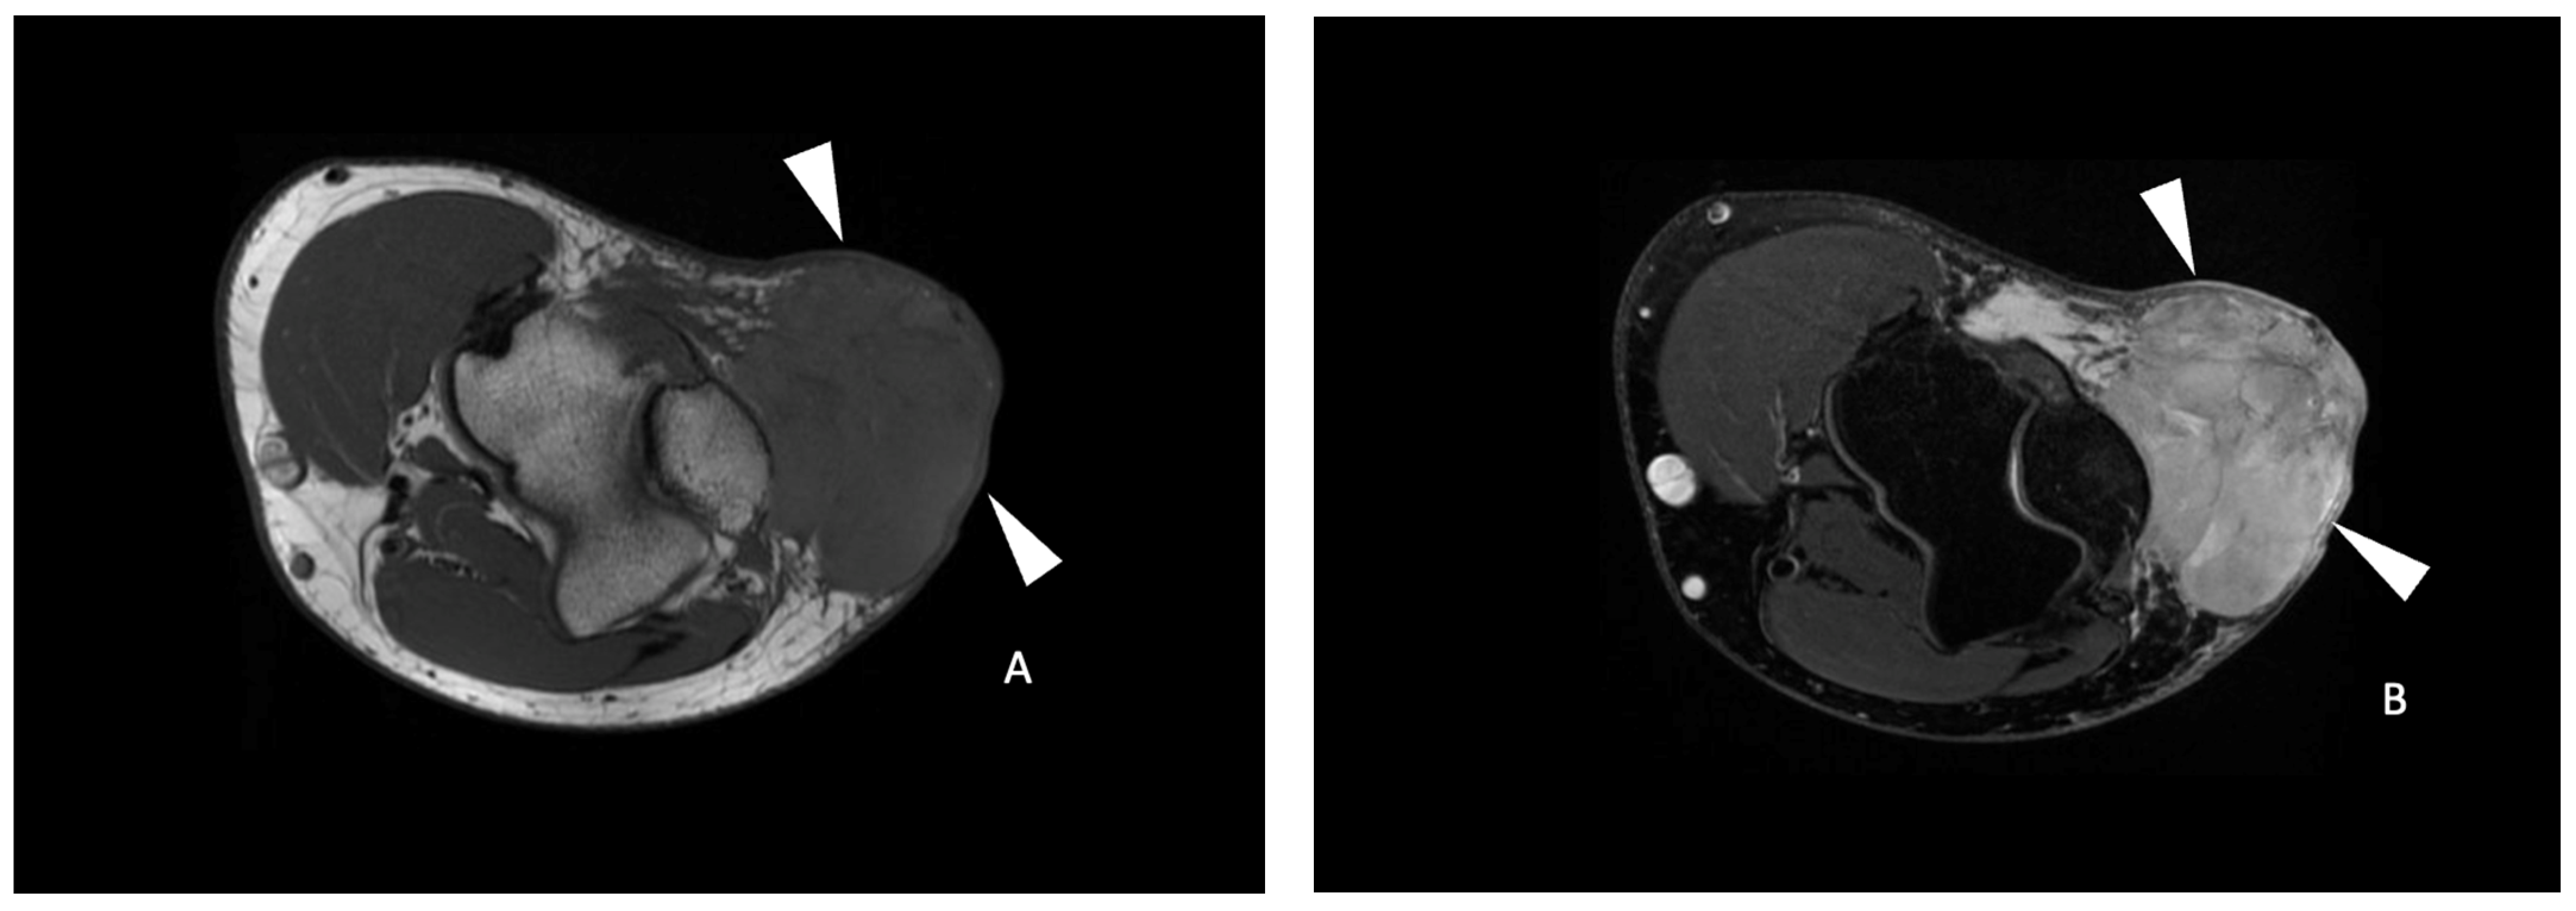

Figure 1.

Functional imaging post-processing and analysis in a 69-year-old male with a leiomyosarcoma of the left popliteal fossa. Sagittal T2-weighted fat-saturated (A) and axial T1-weighted contrast-enhanced (B) MR images showing an ovoid mass (white arrowheads) with a heterogeneous hyperintense T2 signal and enhancement of the posterior compartment of the thigh in the popliteal fossa. (C) DCE (dynamic contrast-enhanced) AUC (area-under-the-curve) functional map in the axial plane showing a homogeneously enhancing tumor (arrowheads). Two free-form ROIs were placed. One on the area of highest tumor enhancement (green line) and another of the corresponding size in the muscle (white line). (D) Axial ADC (Apparent Diffusion Coefficient) functional map showing the same tumor (arrowheads). (E) An axial ADC functional map with an ROI of the corresponding size was drawn in the muscle (black line).

Figure 3.

A 41-year-old male with a spindle cell sarcoma of the left elbow. Axial T1-weighted (A), axial T2-weighted fat-saturated (B) and axial T1-weighted contrast-enhanced (C) MR images showing an ovoid mass (white arrowheads) with a homogeneous hypointense T1 and hyperintense T2 signal with a heterogeneous enhancement with a central necrotic portion (arrow in (C)) in the superficial soft tissue, with close contact with the aponeurosis and the olecranon process. (D) Axial ADC functional map of the same tumor. A free-form ROI (white line) delineates the tumor area with the lowest ADC identified and was positioned within it, yielding a mean ADC of 92 × 10−3 mm2/s (<161 × 10−3 mm2/s). A free-form ROI (green line) of the corresponding size was positioned in the muscle. The tumor necrosis percentage after neoadjuvant therapy was 0%, corresponding to a poor response to treatment.